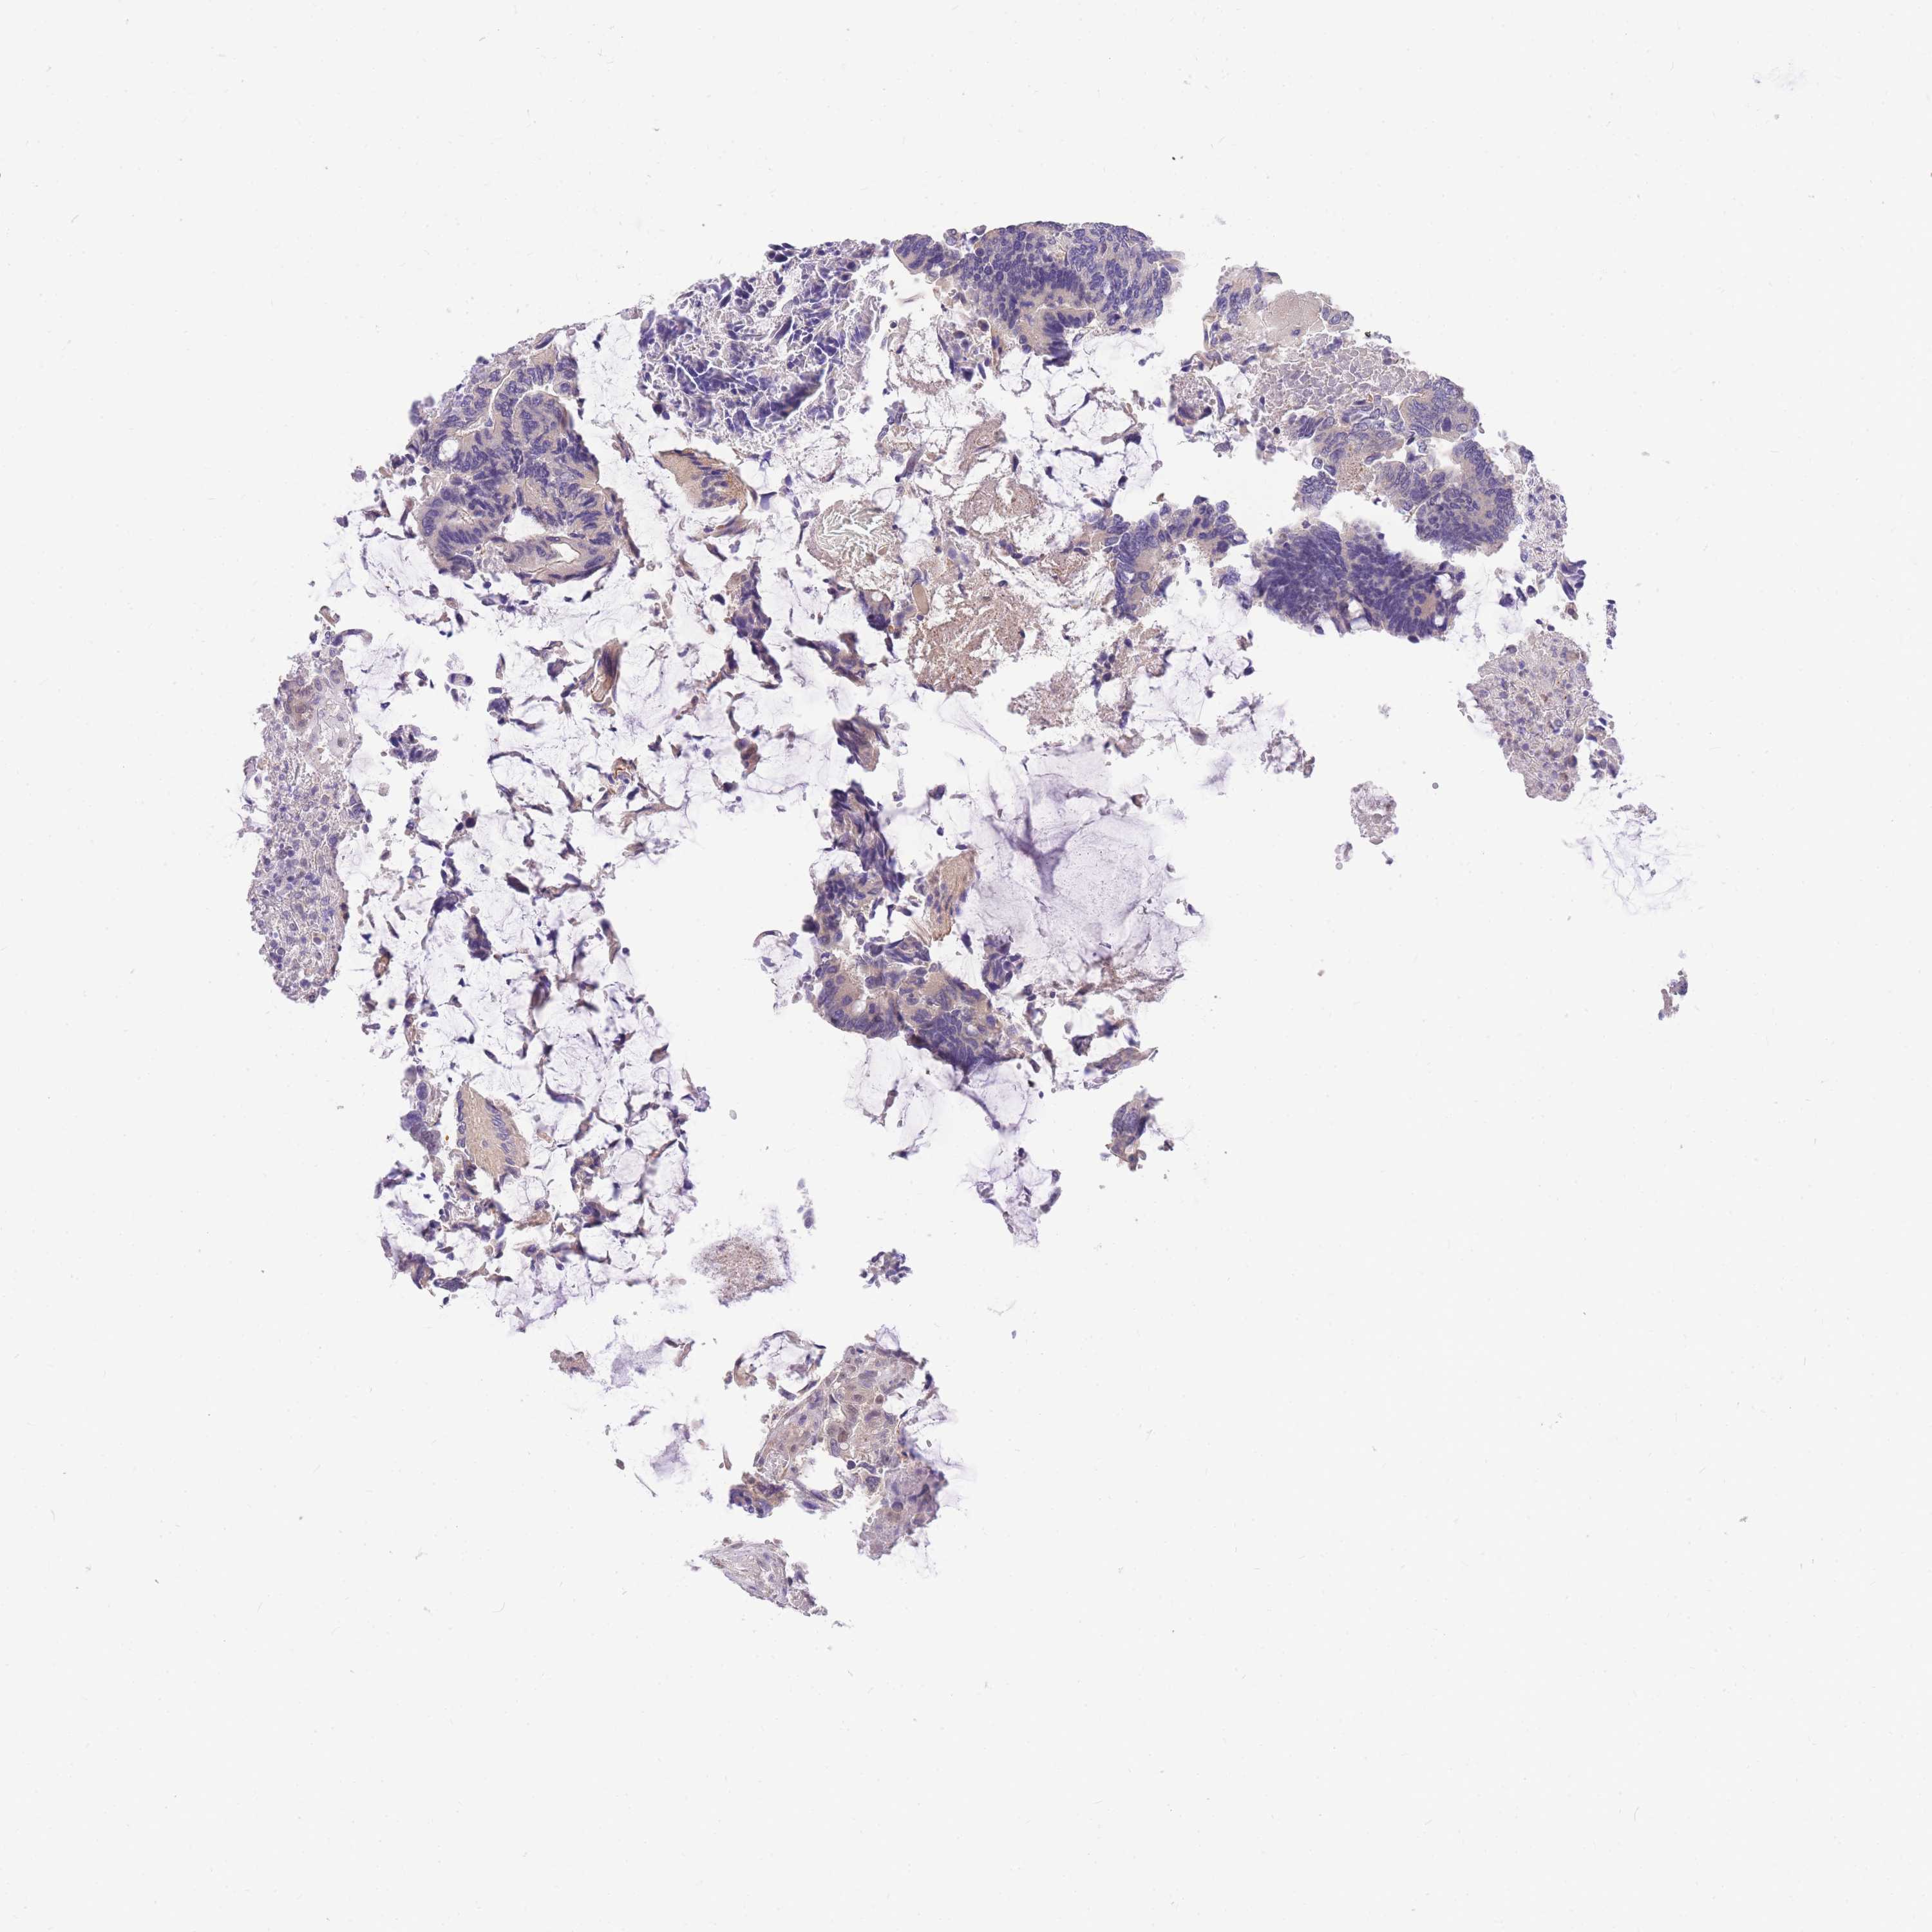

CANCER COLORECTAL CANCER Show tissue menu

Colorectal cancer

Colon adenocarcinoma